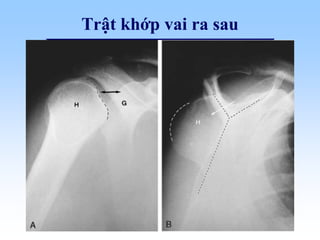

Trật khớp vai

• Trật đầu trên xương cánh tay ra sau 5%:

– Phim trước – sau , cánh tay xoay trong:

• Tăng khoảng cách chỏm xương cánh tay - ổ chảo

• Mất dạng hình cầu của chỏm

– Phim nghiêng:

• Chỏm xương cánh tay di chuyển xuống dưới, ra

ngoài

Trật khớp vai ra sau